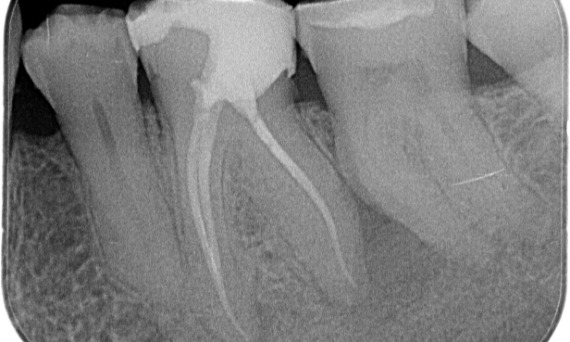

Vorher: Periapikale Radioluzenz primär an der distalen Wurzel und Verlust der Lamina dura an der mesialen Wurzel.

Nachher: In diesem Fall wurde TruNatomy gewählt, um einen kariesfreien Ansatz zu ermöglichen und sich auf den Erhalt des perizervikalen Dentins zu konzentrieren, insbesondere auf der mesialen Seite, wo der Zahn eine minimalere Restauration aufwies.

Bath, Vereinigtes Königreich